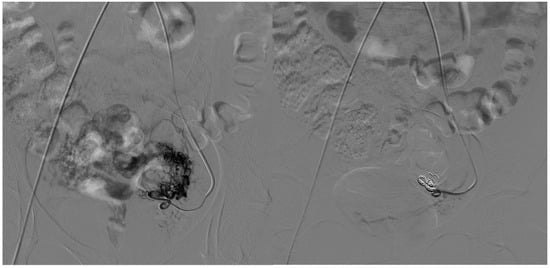

Five patients with Type IV arteriovenous malformations underwent both arterial and venous embolization; all lesions were located in the lower extremity.

On the arterial side, embolic materials were distributed as follows: coils alone in one patient (20%) (Figure 2), a combination of coils and ethylene vinyl alcohol copolymer (EVOH) in one (20%) (Figure 3), EVOH alone in one (20%), and polyvinyl alcohol particles (PVA) alone in one (20%).

Figure 2. A 31-year-old patient presents with a Type IV AVM from the collateral branch of the gluteal artery. The left image shows an angiographic examination performed pre-procedure after super-selective catheterization of the vessel using a Progreat microcatheter. The image on the right shows post-embolization angiography performed using 4 mm coils.

Figure 3. A 33-year-old patient presents with a Type I AVM from the collateral branch of the uterine artery. The left image shows an angiographic examination performed pre-procedure after super-selective catheterization of the vessel using an RUC catheter and a Progreat microcatheter. The image on the right shows post-embolization angiography performed using three 6 mm Nester coils and injecting EVOH.